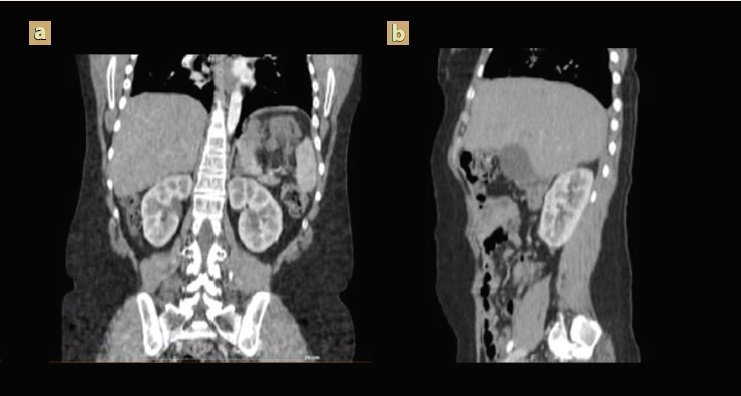

Presentó una evolución satisfactoria en su postoperatorio, tomografía axial de abdominal de control sin nuevas imágenes tumorales (figura 3); acudió con reporte definitivo de patología con teratoma quístico maduro sin evidencia de neuroepitelio en la totalidad de la muestra hepática y tumoraciones retroperitoneales resecados, marcadores tumorales se encuentran negativos, dado los antecedentes de teratoma inmaduro y en este caso las lesiones presentaron tejido maduro derivado de las 3 capas germinativas, sin atipias, lo cual corresponde a síndrome de teratoma en crecimiento. No requirió manejo adicional con quimioterapia, presentó una adecuada evolución.